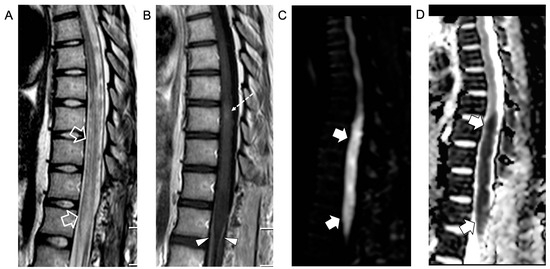

An urgent spinal magnetic resonance imaging (MRI) scan showed acute transverse myelitis extending from D7 to D10, associated with contrast enhancement of the anterior and posterior roots of the cauda equina, indicative of myeloradiculitis (Figure 1).

Figure 1.

Contrast-enhanced spinal MRI performed at clinical onset. Sagittal T2-weighted (A) and post-contrast T1-weighted (B) images; axial T2-weighted (C) and post-contrast T1-weighted (D) images. There is a T2 hyperintensity in the central portion of the spinal cord (empty arrows in (A) and thin arrow in (C)) in keeping with an acute transverse myelitis extending from D7 to D9, associated with a faint area of contrast enhancement at the D8 level (thick arrow). Note the contrast enhancement of the anterior and posterior cauda equina nerve roots (arrowheads) indicative of myeloradiculitis.